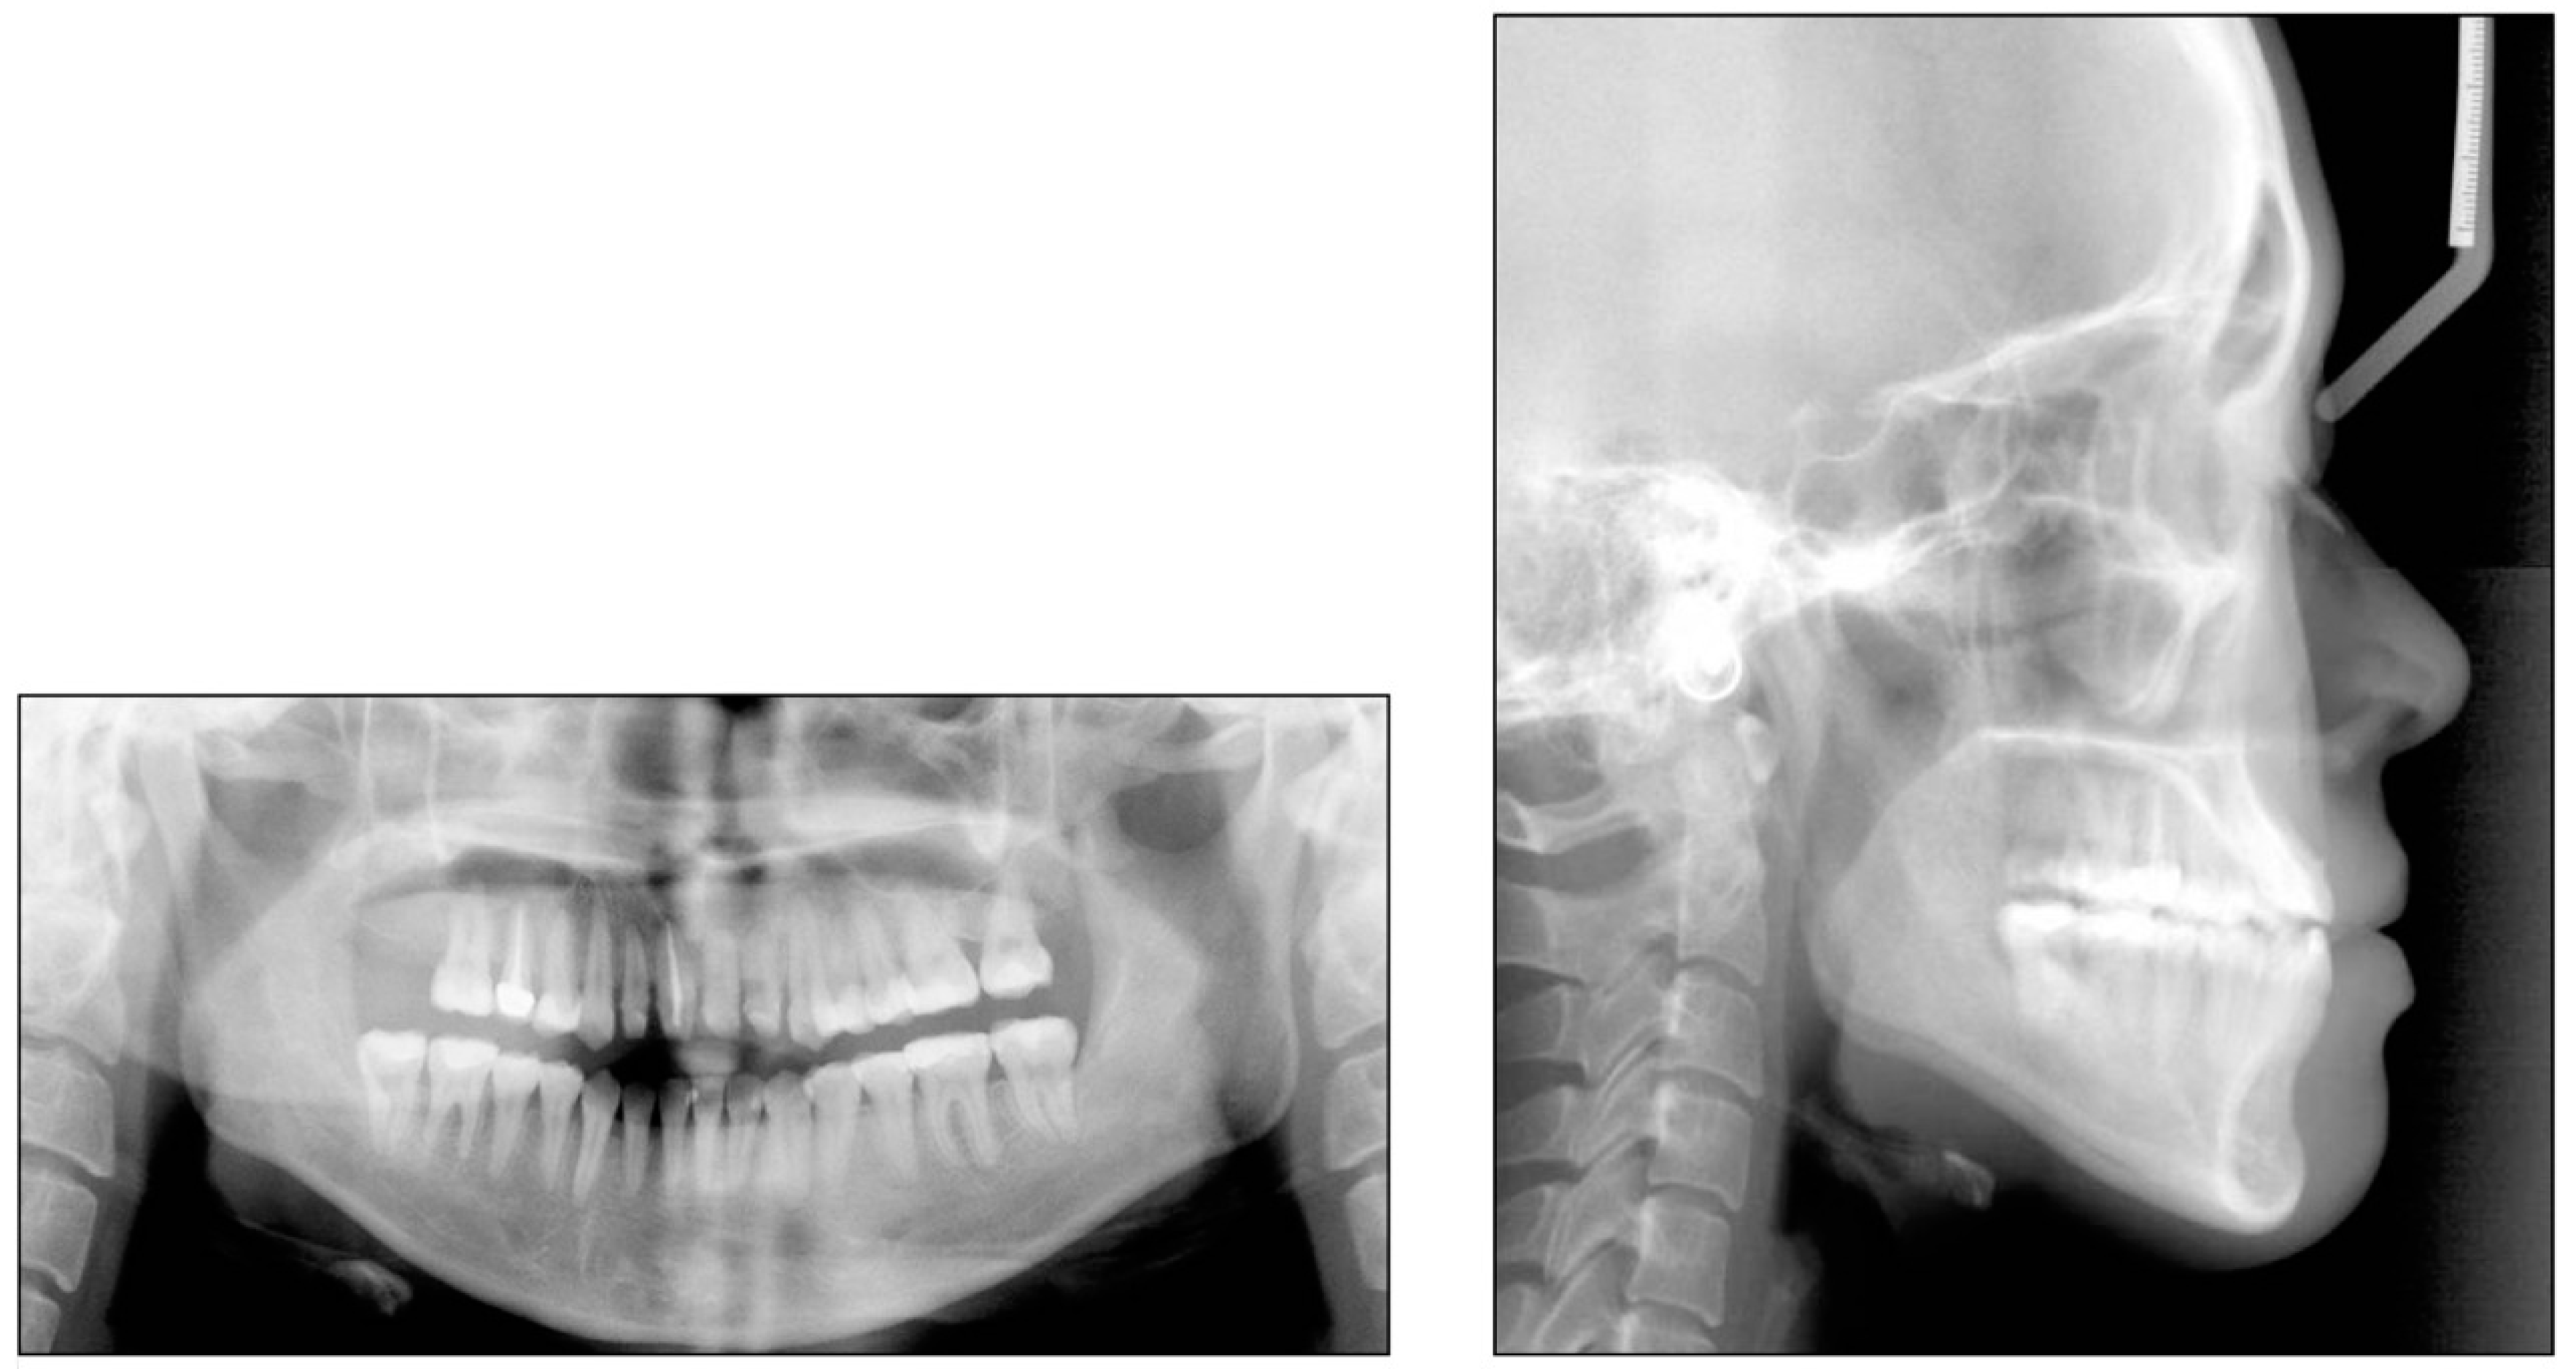

2. Case 1

2.1. Diagnosis and Etiology